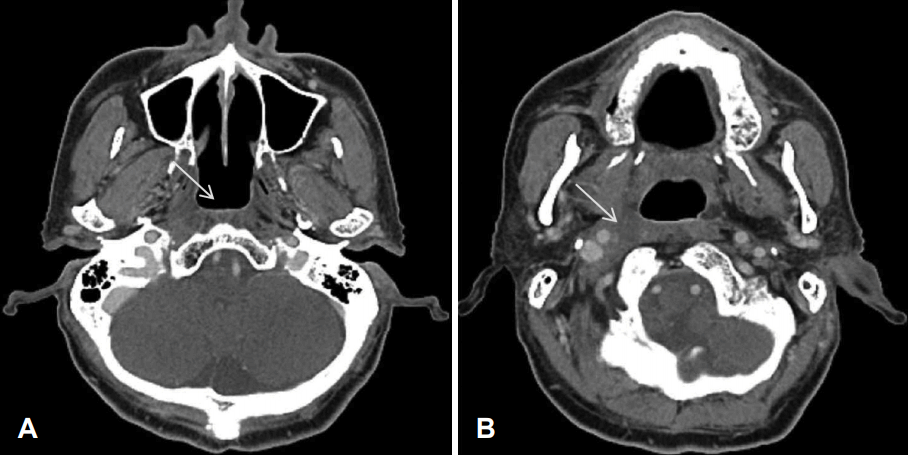

Fig. 1.

CT axial views at 7 years ago when the patient was referred to ENT clinic, contrast enhanced CT axial image shows (A) intact nasopharynx, implying no recurrence of cancer (arrow) (B) but, 21×21 mm sized heterogeneous enhancement lesion on right retropharyngeal lymph node (arrow).